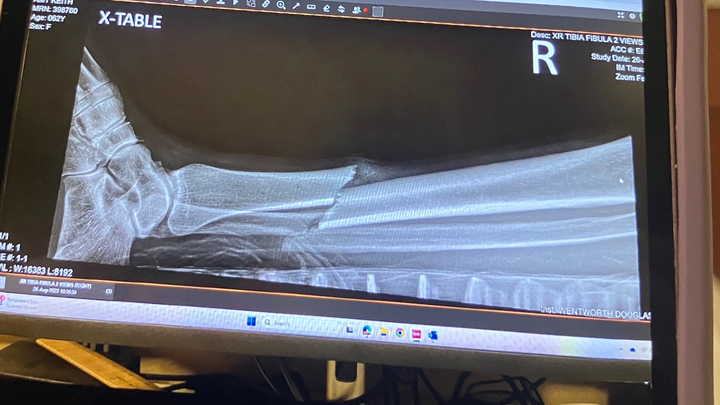

there i was, out on an epic early morning trail ride with a couple of stablemates, when one of their horses fired a hoof out and got me in the shin. i'm speculating the bugs were pissing her off and she didn't really know my horse. no sense getting mad about it, i'ts done. i actually quite like the mare. i knew instantly it was broken. after an initial 'fight' response by my horse, she got a grip and carried me back to the barn, like the wounded soldier i was. she's used to sidling up to our mounting block for me to dismount, so that wasn't weird for her. i swung my bad leg over her back, landing on my good one. with considerable assistance, i got into a car and was transported to the ER at Wentworth Douglass Hospital.

they called me a blessedly short time after arriving. it was an open wound so surgery had to be immediate. i had not eaten and drank only sparsely that morning so that was good, and there was a good leg doc available. damage control was going well. next thing i know, i'm sporting a titanium rod from knee to ankle with a screw at each end. i am SO grateful for modern medicine and good surgeons, not to mention my beloved barn family, who have been killing me with loving kindness and delicious food since coming home.